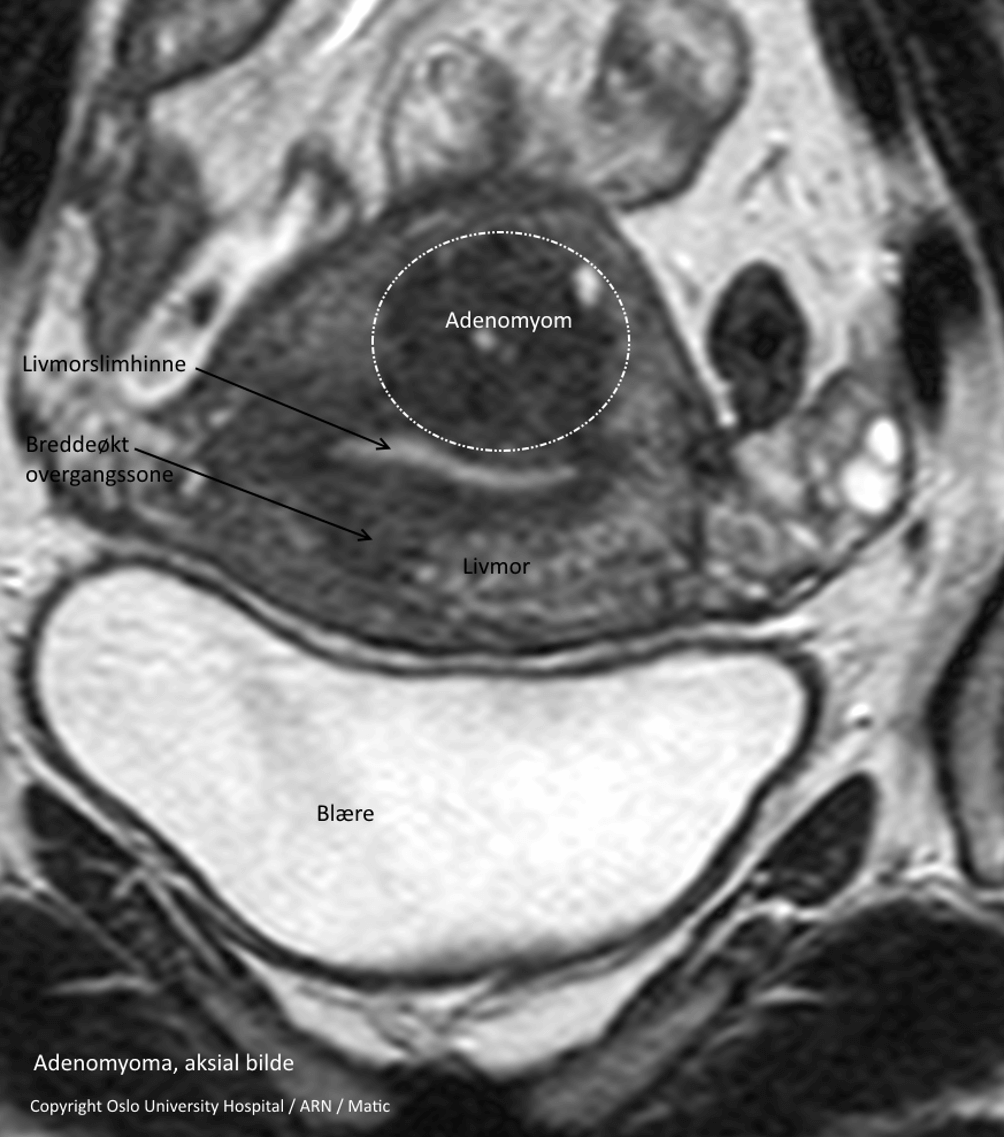

Det er også muligt at stille diagnosen ved en MR-scanning. Med denne metode kan ca. 90% af alle tilfælde blive diagnosticeret korrekt, forudsat at den rigtige undersøgelsesprotokol vælges, og at undersøgelsen bliver gennemført med god kvalitet.

Hvis lægen er usikker på diagnosen efter en indvendig ultralydsundersøgelse, kan der foretages en MR-scanning.